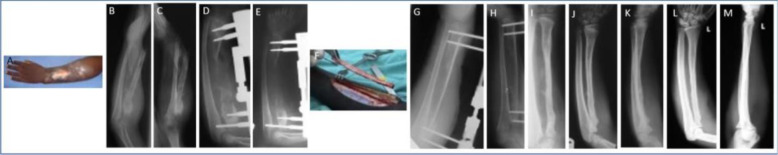

Abstract Image

Background. Post-osteomyelitis bone defects represent a challenging clinical situation. This retrospective cohort study was designed to evaluate the long-term outcome of the use of non-vascularized bone grafts in the management of such defects in children. Methods. Twenty-three children (mean age 7 years, range 2-13 years) were studied. All of the defects were segmental (mean defect length 6 cm, range 3-12 cm), involving the tibia, femur, humerus and radius. Fifteen children presented with an active infection and were managed with a staged protocol. The first stage included sequestrectomy or debridement of the site. The second stage, i.e. the graft procedure, was performed after 12 weeks on average. The mean follow-up was 9.2 years (range 7-15 years). Results. Bone union was primarily achieved in 14 children (61 %). Complications were experienced in the remaining nine children. Conservative and surgical treatment led to bone union in all patients within 5 years of the index procedure. Recurrence of infection was observed in two patients (8.7 %). All of the children were able to use the limb at the final follow-up; only three required the use of a brace. Conclusions. Autogenous non-vascularized bone graft may be considered a valid option in the treatment of bone defects secondary to osteomyelitis in children.